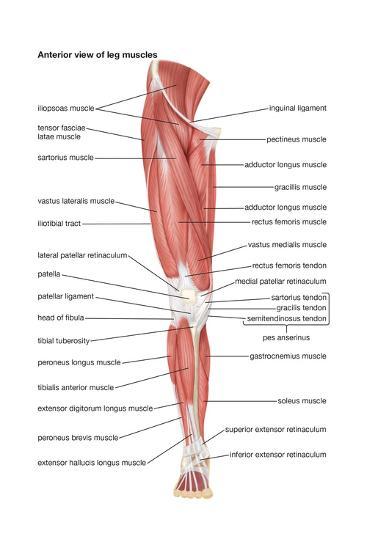

human leg muscles anatomy

'The Anterior View Of The Muscles Of The Human Right Leg' Poster

www.allposters.com

www.allposters.com